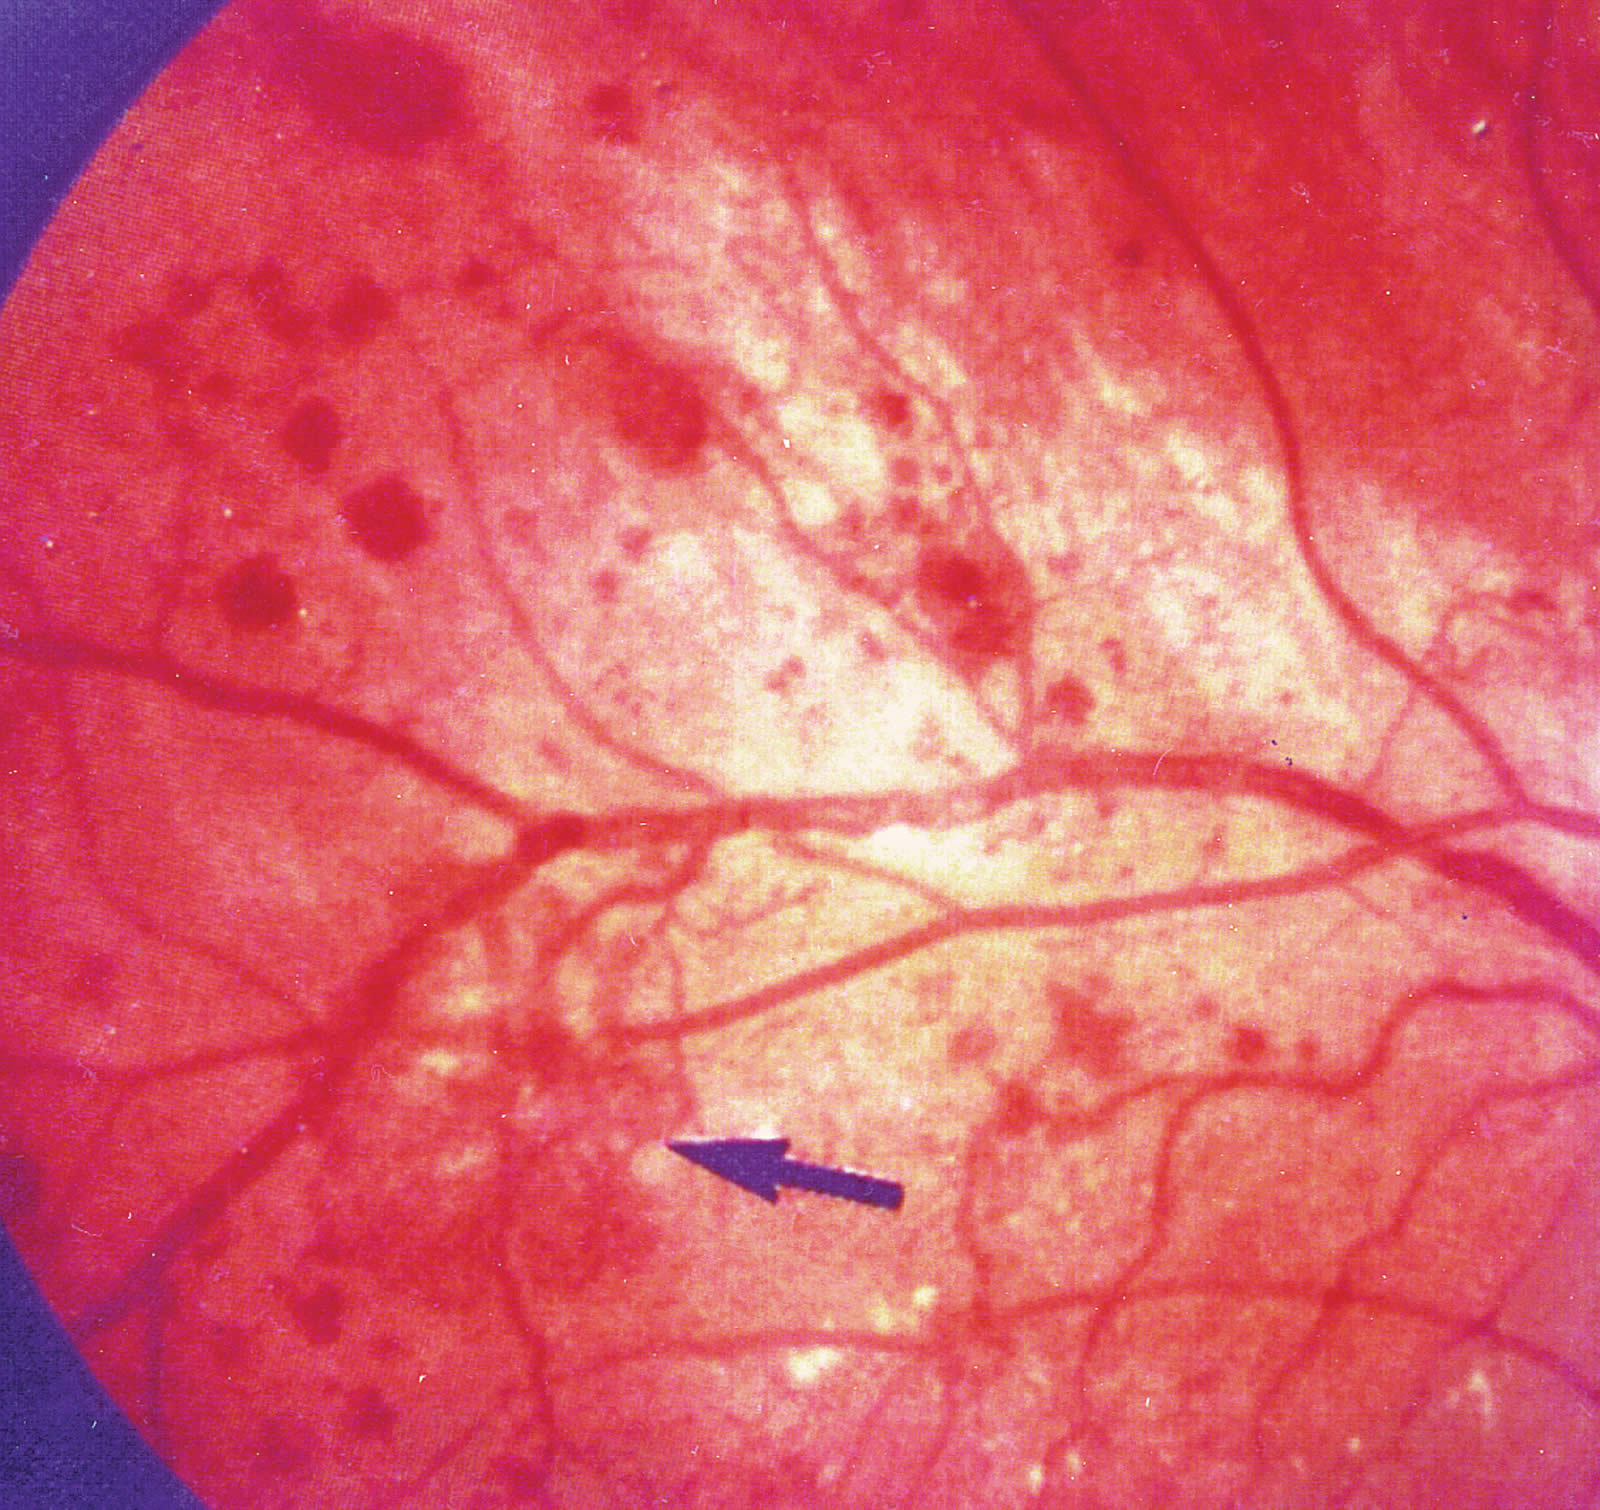

The following photographs show non-proliferative and macular diabetic retinopathy.

- Diabetic maculopathy (Figure 2).

Diabetic maculopathy

Diabetic retinopathy situated in and around the macula is described as diabetic maculopathy, which can result in significant visual impairment. All these background diabetic retinal changes are due to pathology occurring at the microvascular level of the retina, including dilatation of the capillaries, destruction of the capillary walls and closure of the capillaries resulting in hypoxia and micro-infarcts.

The Early Treatment of Diabetic Retinopathy Study (ETDRS) classified patients who were given macular focal laser therapy, based on whether ‘clinically significant macular oedema’ was present or not.12,13,15 This was classified as:

- Retinal thickening at or within 500µ (one third of the diameter of the optic disc) at the centre of the macula

- Hard exudates at or within 500µ of the centre of the macula, if there is thickening of the adjacent retina

- An area of retinal thickening greater than one optic disc area in size, at least a part of which is within one disc diameter of the centre of the macula.